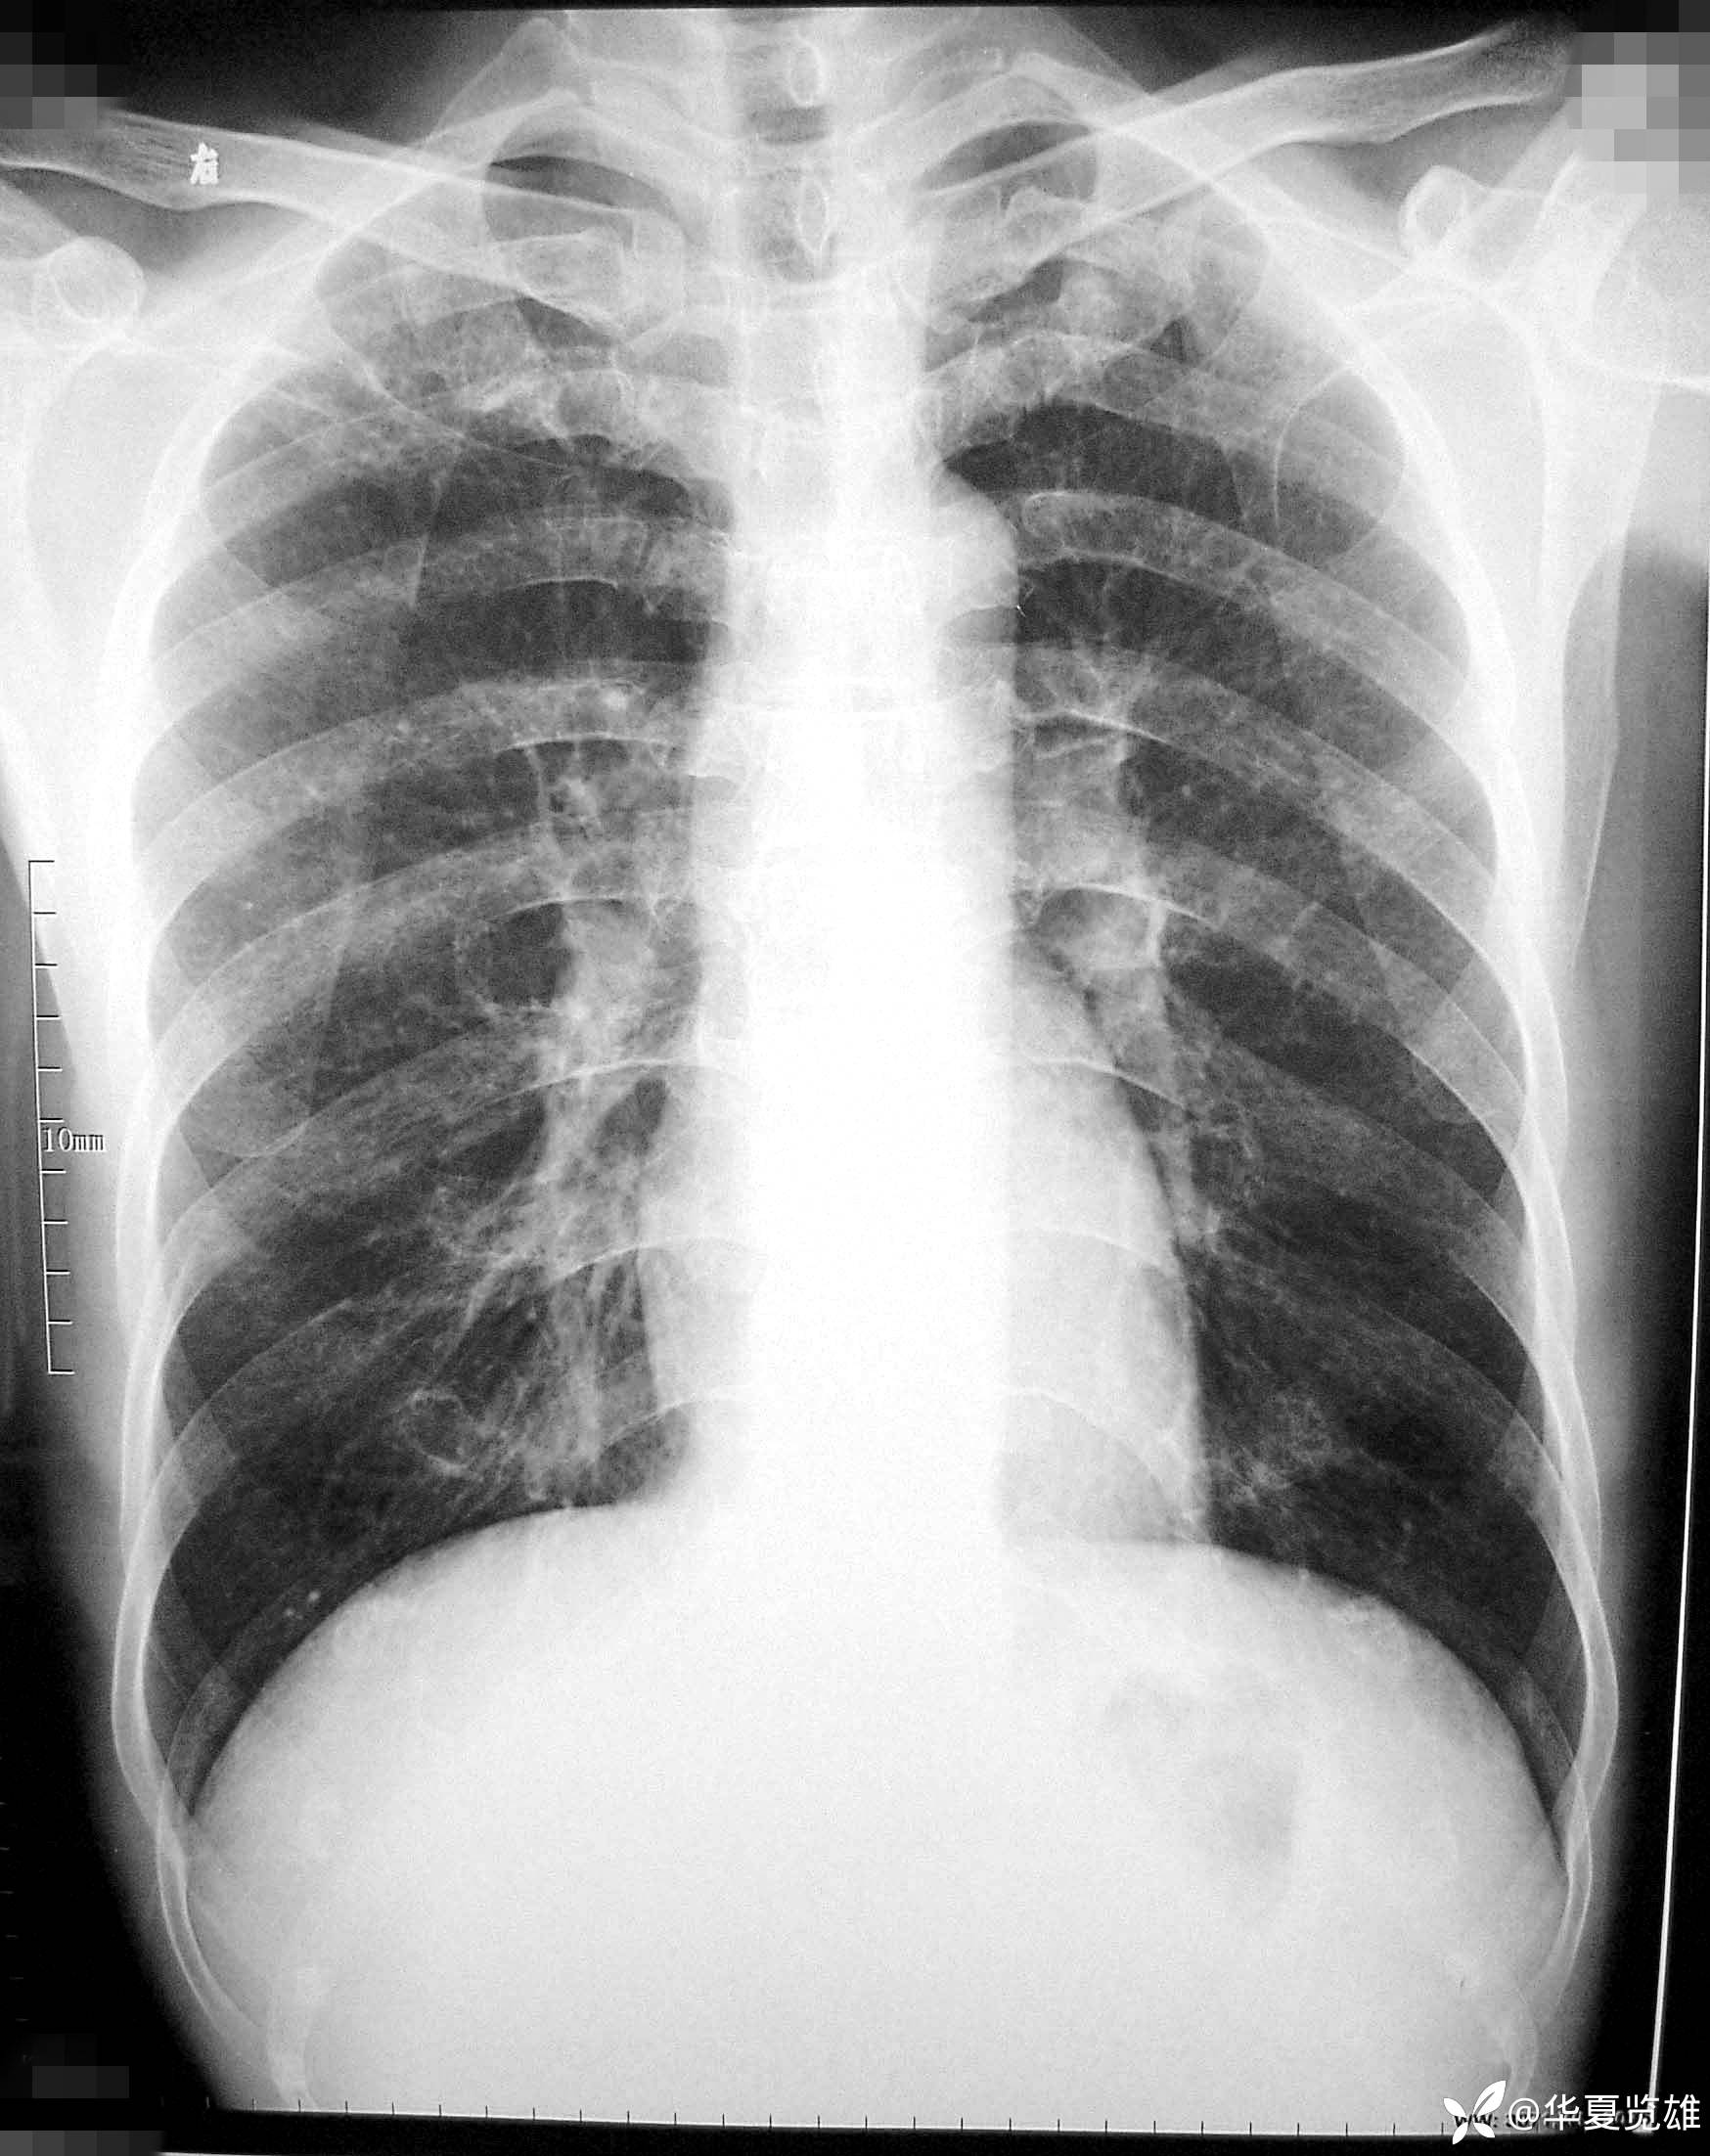

患者性别:男

患者年龄:48岁

主诉:咳嗽23天,痰中带血3天。

简要病史:患者三周前咳嗽,痰量少。有时伴有发热,体温37.5℃-38.5℃。自服抗生素体温降至正常。

辅助检查:血常规、肿瘤标志物未见异常。

临床诊断:肺内感染

先上平片,请仔细观察,是否有异常。CT在公布结果里。